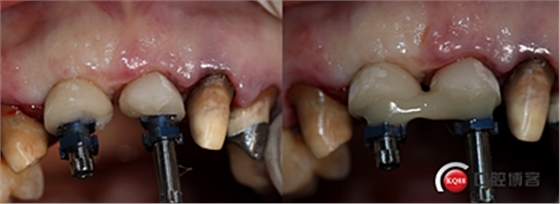

制作個性化轉(zhuǎn)移桿,對齦緣壓迫塑形。

取模。

全瓷冠制作完成,齦乳頭預留空間不足,修整三角間隙。